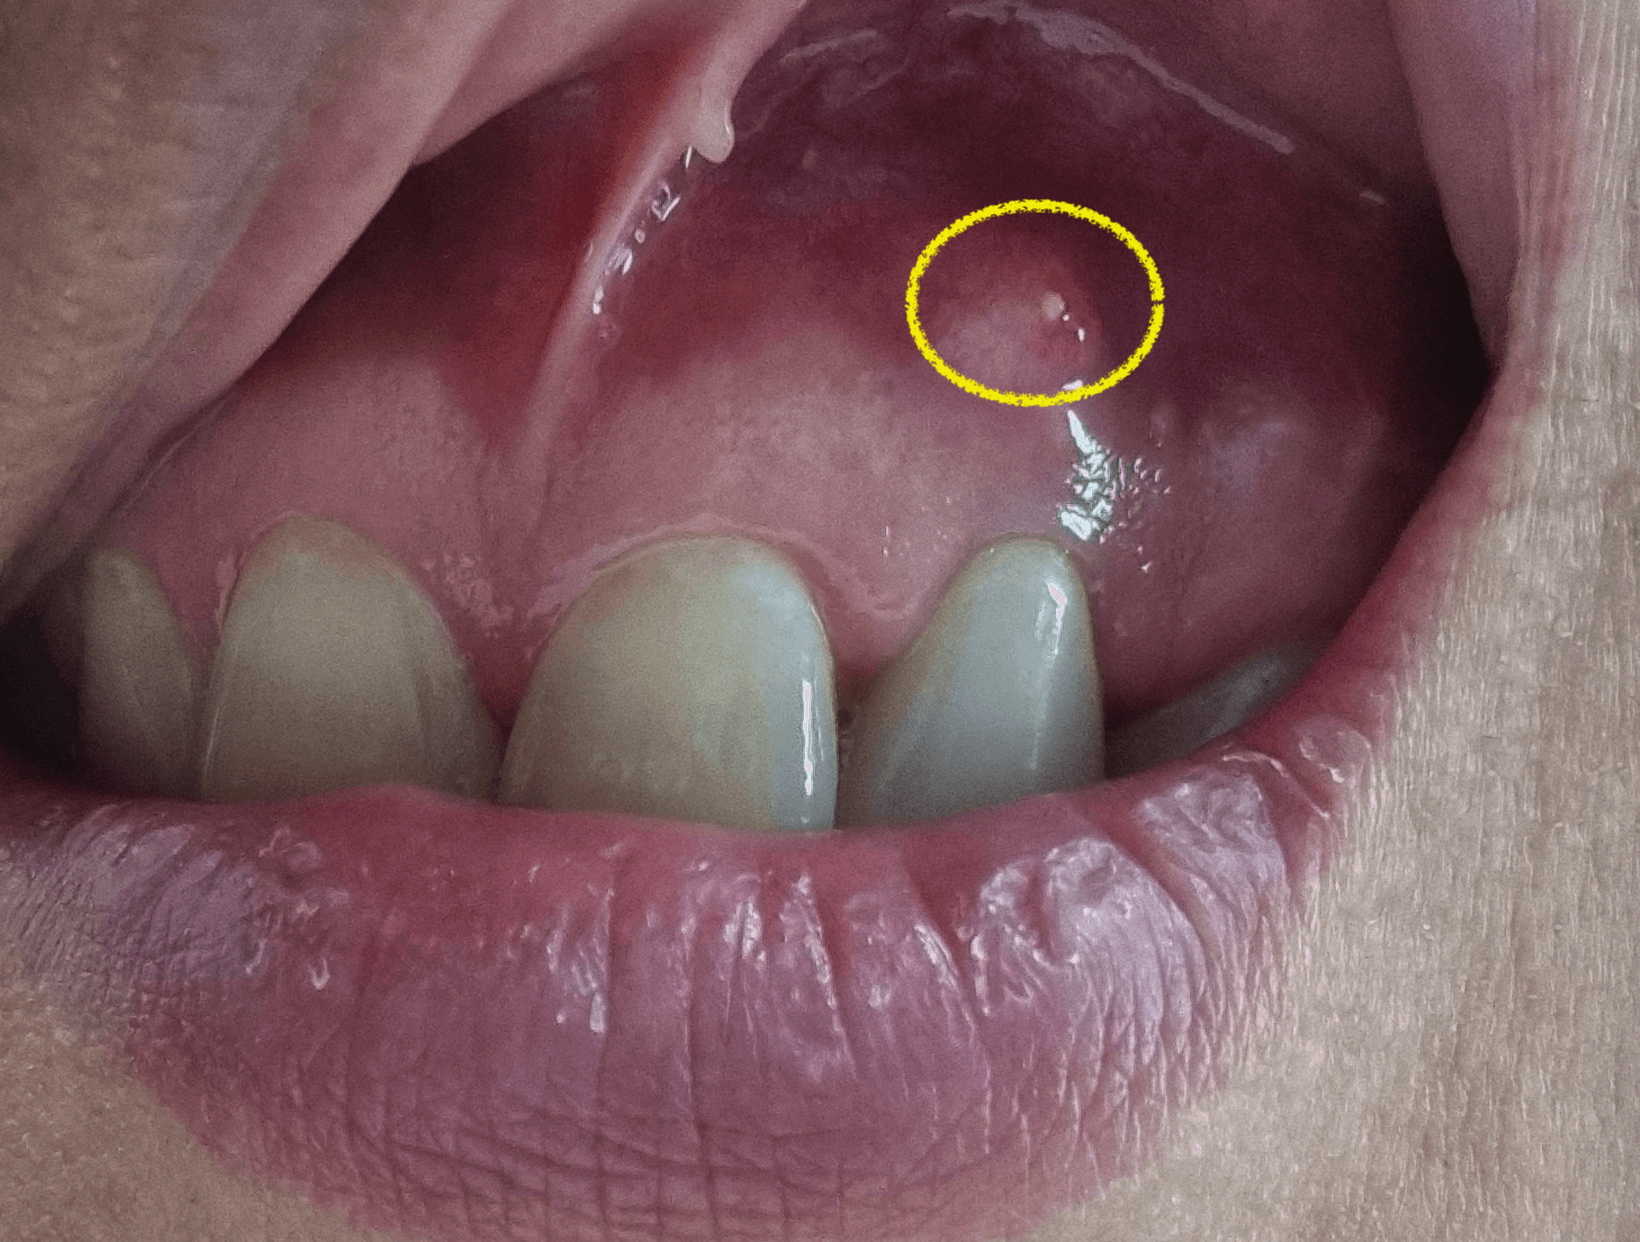

치근단절제술 수술을 한지 1년이 다된 지금 해당 앞니 치근단절제술을한 그부분에 잇몸이 다시 한번 불룩하게 티어 올라온것이 보였습니다. 그것은 딱봐도 염증이 차서 부어오른것이며, 저처럼 치근단절제술을 시행후 염증이 재발한 상황에 대한 내용을 의사가 아닌 환자로써 염증 재발 후기에 대한 정보를 공유 합니다.

1년정도 전에 치근단절제술을한 치아에서 다시 문제가 생겼습니다. 보통 3개월이 지나서 염증이 나오지 않으면 대부분 성공이라 생각하고 별일 없는이상 염증에 재발하지 않을거라 생각을 합니다.

그런데 저같은경우 기존에 염증 크기가 뼈이식을 할만큼 큰 낭종크기정도의 염증이라서 결국 염증이 완전하게 사라지지 않고 다시 다양한 사유로 인해 재발하게 된것 같다고 의사 선생님이 이야기를 했습니다.

그래서 치과 선생님께 여쭈어 보았던 내용이, 이 염증이 여기에 계속 있으면 저번처럼 뼈를 계속 녹이냐고 물어보니, 저같은 경우 염증이 예전처럼 안에 계속 있는게 아니라 터지면서 계속 흘러나오니 이전처럼 뼈를 녹이지는 않을것이다.

글쓴이님 같은경우 염증이 워낙커서 기억에 남는 사람이고, 아쉽게도 염증이 재발을 했는데, 통증이 없고 염증이 생겨도 안에서 터져 흘러 나오기 때문에 이전처럼 안에서 뼈를 녹인은 상황은 만들어 지지 않을것이다.